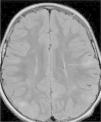

In the 74.3% (26) patients for whom MRIs were available, 76.9% (20) of them had tubers in every cerebral lobe and more than 15 tubers in total, thus presenting high lesion load. Radial migration lines were observed in 96.2% (25) of the patients (Fig. 1). Subependymal nodules were found in 84.6% (22), most of them calcified, and 3 of them enhancing (Fig. 2). Infratentorial tubers were found in 23.1% (6) of the patients. Cyst-like tubers were present in 7 (26.9%) patients, with juxtacortical location in 6, and infratentorial location in 1 (Fig. 3). There was one probable case of giant cell astrocytoma, around the foramen of Monro, measuring less than 1cm, without hydrocephalus (Fig. 4). Focal atrophy was not found in any of the patients.

We reviewed the MR studies of all patients with an identified TCS2 mutation except one, and found a high lesion load in all of them. One of the 5 patients with a TSC1 mutation had a high lesion load. Of the 5 cases associated with refractory epilepsy, 2 had cyst-like tubers.

FLAIR images were used to identify tubers and radial migration lines,18 and T2-weighted FLAIR images to identify subependymal nodules.

Tubers were defined as corticosubcortical lesions with high signal intensity on FLAIR images, and radial migration lines as lines of hyperintensity on FLAIR images extending from the ventricles to tubers in the cortex. Subependymal nodules were found in all ventricles, protruding into the ventricles from the ventricular wall.